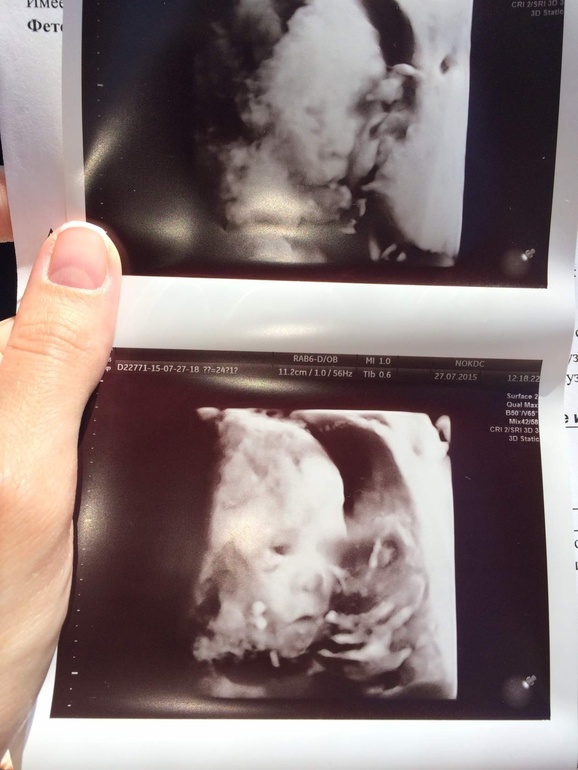

24 неделя. Мой шладкий)))))

УЗИ, КТГ, доплерПошла на узи посмотреть, рассосались ли кисты сосудистых сплетений головного мозга, которые нам насмотрели в 18,5 недель. К генетику не пошла. Сейчас все рассосалось. Все соответствует сроку. На момент узи, 2 недели назад, был 590 гр.)

"....На момен узи 2недели назад -590гр???? "Тоес ь в 22 недели или в 24 все таки ??!!

Большой такой!!))